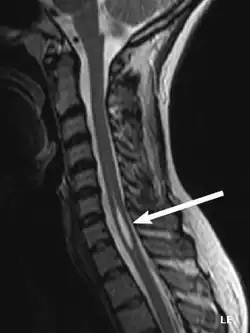

| An idiopathic syrinx | |

Physicians now use magnetic resonance imaging (MRI) to diagnose syringomyelia. The MRI radiographer takes images of body anatomy, such as the brain and spinal cord, in vivid detail. This test will show the syrinx in the spine or any other conditions, such as the presence of a tumor. MRI is safe, painless, and informative and has greatly improved the diagnosis of syringomyelia.[18]

The possible causes are trauma, tumors, and congenital defects. It is most usually observed in the part of the spinal cord corresponding to the neck area. Symptoms are due to spinal cord damage and include pain, decreased sensation of touch, weakness, and loss of muscle tissue. The diagnosis is confirmed with a spinal CT, myelogram or MRI of the spinal cord. The cavity may be reduced by surgical decompression.[22]